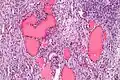

| Micrograph of a struma ovarii. Characteristic thyroid follicles are seen on the right, and ovarian stroma on the left. H&E stain. | |

A struma ovarii (literally: goitre of the ovary) is a rare form of monodermal teratoma that contains mostly thyroid tissue, which may cause hyperthyroidism.[1]